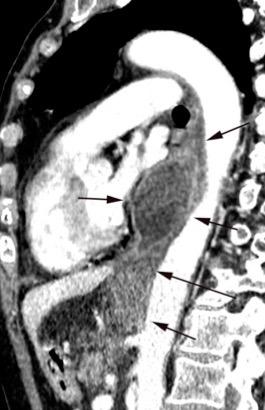

Ganglios retroperitoneales (flechas negras)

germinales del testículo izquierdo Nódulos pulmonares múltiples. (flechas verdes). Ganglios paratraqueales. (flechas amarillas). Dudoso ensanchamiento retrocrural (flechas negras)

Panda A et al. “Straddling Across Boundaries”. Thoracoabdominal Lesions: Spectrum and Pattern Approach. Curr Probl Diagn Radiol, 2015